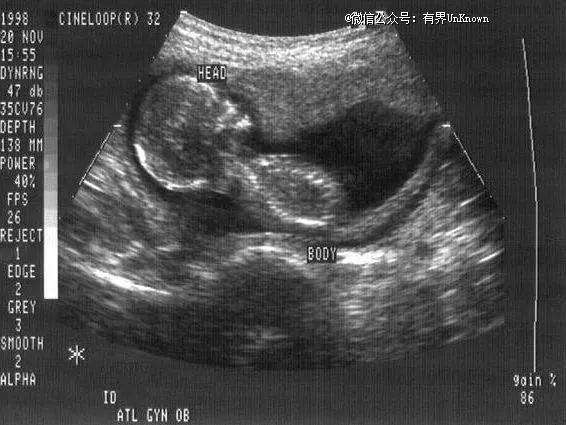

▲ 孕妇怀孕期间的B超图像

如果我们认真来拆解,其实会发现“机器人妈妈”主要有两个组成部分:一个机器人本体,一个人造子宫。